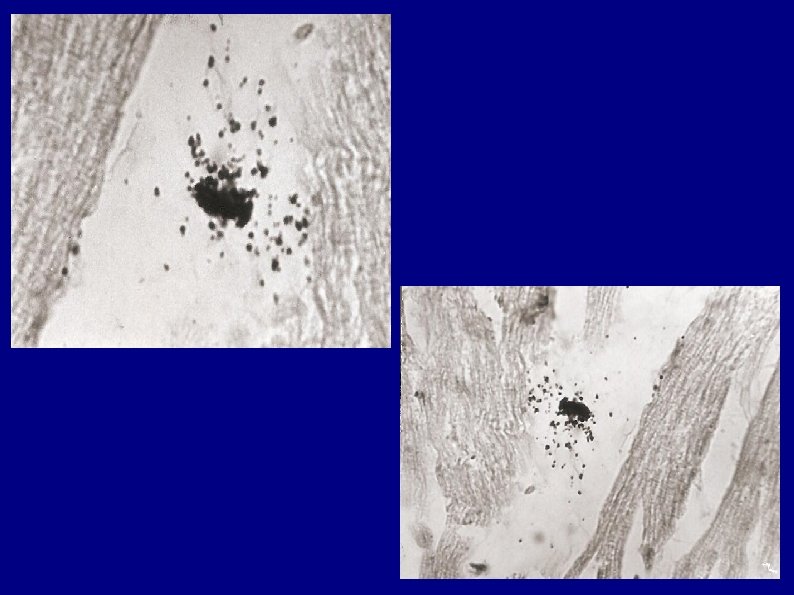

Otros trabajos de nuestro equipo fueron dedicados a estudiar el tipo y número de las células infiltradas en el corazón humano en la cardiopatía chagásica Hallamos predominio de linfocitos T, seguidos por macrófagos. También verificamos un incremento de células cebadas ( mastocitos). El predominio de esas células inmunológicas se corroboró en todos los casos de una casuística numerosa indicando su participación en los mecanismos inmunopatológicos de daños en esa cardiopatía chagásica.

Células cebadas (Mastocitos) en corazón chagásico

Hallazgo de neomicrovasculatura en la cardiomiopatía chagásica Otro hallazgo que efectuamos en estos trabajos fue que en áreas de lesiones de Chagas, hallamos microvasos similares a los que hay en ganglios linfáticos normales y permiten un intenso pasaje de linfocitos (Vénulas de Endotelio Alto)las cuales fueron originalmente descriptas por Thomé en 1898.

Hallazgo de neomicrovasculatura en la cardiopatía Chagásica También hallamos que en las áreas de lesiones chagásicas intracardíacas se produce una proliferación de pequeños vasos, juntamente con Vénulas de Endotelio Alto, con pasaje de linfocitos al intersticio. Esos aspectos fueron distinguidos por el premio 25 Años del Consejo de Chagas, “Dr Salvador Mazza “de la Sociedad Argentina de Cardiología, Buenos Aires, octubre de 2004